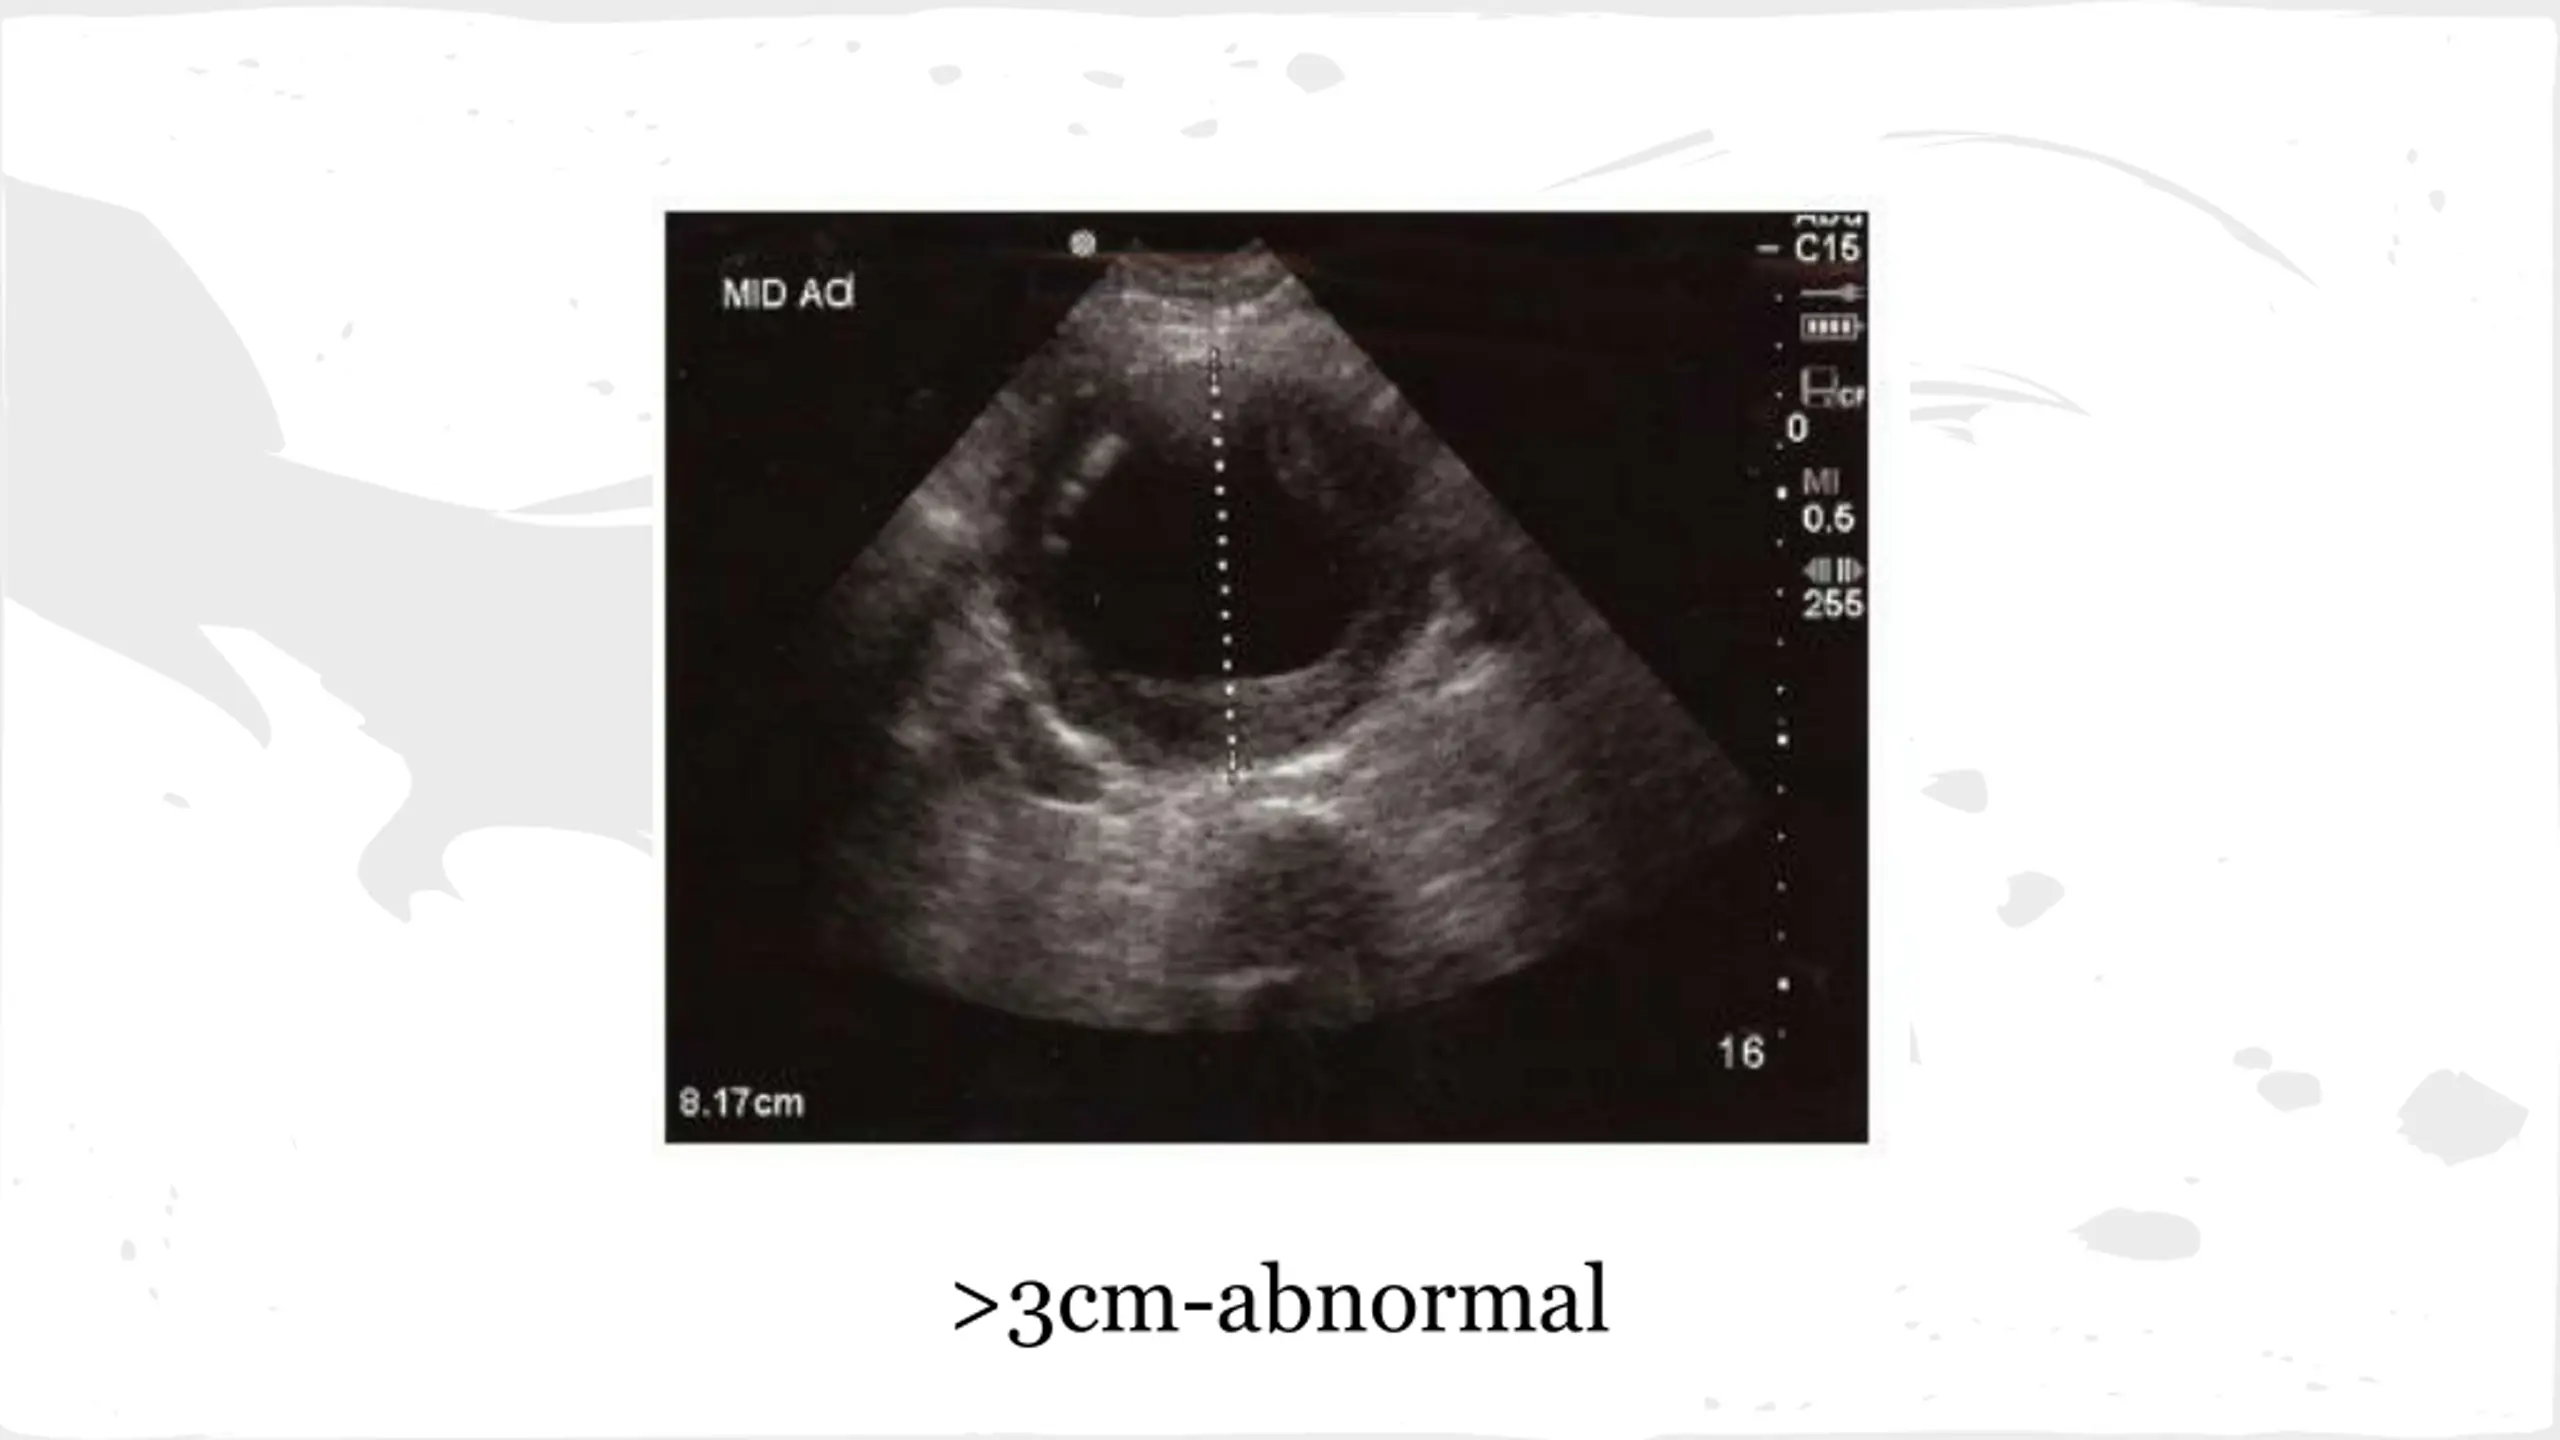

AAA Risk Factors Smoking Male Gender Age over 65 HTN HLD Symptoms Abd, Flank or Back Pain-can mimic renal colic Syncope or Dizziness-due to low BP

AAA Tests US is test of choice CT is useful for surgeons to plan procedure CBC Type and Screen-transfuse if ruptured Pre op labs Management-Rupture Surgical Repair Volume resuscitation Target Systolic 90-100